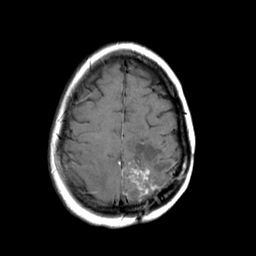

MR Study #3 -- Slice #41

[Home][Help][Clinical][Tour 1][Tour 2][Tour 3] Slice 41